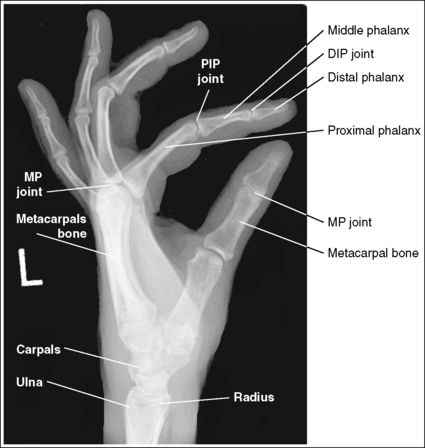

See Figure 4-22 and Box 4-8.

The digits and metacarpals demonstrate a PA projection. The soft tissue outlines of the second through fifth phalanges are uniform, the distance between the metacarpal heads is equal, and the same midshaft concavity is demonstrated on both sides of the phalanges and metacarpals of the second through fifth digits.

• A PA projection of the hand is obtained when the patient fully extends the hand and rests the palmar surface flat against the IR (Figure 4-23).

• PA versus external oblique hand position. If the hand is not fully extended but is slightly flexed, it often relaxes into an external PA oblique projection when it is resting against the IR. A PA oblique hand projection is signified by slight superimposition of the third through fifth metacarpal heads and unequal soft tissue thickness and midshaft concavity on the sides of the phalanges. The metacarpals also show unequal midshaft concavity and spacing (see Image 20). Abducting the patient's arm and placing the forearm and humerus on the same horizontal plane, with the elbow flexed 90 degrees, assists in preventing an externally rotated PA oblique projection and will best demonstrate the wrist. This is important if a wrist condition is causing radiation hand pain. When the patient has been positioned in this manner, the ulnar styloid appears in profile on the image. Internal rotation of the hand is seldom a problem, because the thumb prevents this movement.

No soft tissue overlap of adjacent digits is present.

The IP, MP, and CM joints are visible as open spaces, and the phalanges and metacarpals are not foreshortened. The thumb is demonstrated in a 45-degree PA oblique projection.

• When the hand and fingers are fully extended and a perpendicular central ray is centered to the third MP joint space, the IP, MP, and CM joints are demonstrated as open spaces and the phalanges and metacarpals are seen without foreshortening on the PA hand projection.

The third MP joint is at the center of the exposure field. The distal, middle, and proximal phalanges, the metacarpals, the carpals, and approximately 1 inch (2.5 cm) of the distal radius and ulna are included within the collimated field.

• Center a perpendicular central ray to the third MP joint to place it in the center of the collimated light field. This MP joint is situated just slightly distal to the head of the third metacarpal. Once the central ray is centered, open the longitudinal collimation to include the distal phalanx and 1 inch (2.5 cm) of the distal forearm. Transversely collimate to within 0.5 inch (1.25 cm) of the first and fifth finger's skin line.